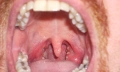

V některých případech ano, ale vždy je nutné nejprve vyloučit zvětšené mandle.

Homeopatika na chrápání

Homeopatie vychází z principu individuální léčby člověka jako celku, nikoli pouze jednoho příznaku. U chrápání se proto neřeší jen samotný zvukový projev, ale především příčina zúžení dýchacích cest, svalové ochabnutí, otok sliznic nebo poruchy spánku.

Homeopatika se nejčastěji uplatňují u osob, které netrpí spánkovou apnoí, nemají závažné anatomické vady a hledají přírodní léčbu chrápání bez vedlejších účinků.

Nejčastěji používaná homeopatika na chrápání

Výběr homeopatika se vždy odvíjí od konkrétních obtíží. Níže uvádíme nejčastěji doporučované přípravky při chrápání.

Opium

Vhodné při hlubokém, hlučném chrápání, kdy člověk spí velmi tvrdě, má zpomalené dýchání a špatně reaguje na probuzení. Často se používá u osob s nadváhou.

Lachesis muta

Doporučuje se při chrápání zhoršujícím se v poloze na zádech, pocitu sevření v krku a při nočním buzení. Typické je zhoršení obtíží v teple.

Kalium bichromicum

Vhodné při chrápání spojeném s hustým hlenem v nosohltanu, chronickou rýmou nebo ucpaným nosem, zejména v noci.

Nux vomica

Často se používá u lidí, kteří chrápou po alkoholu, těžkých jídlech nebo při stresu. Typické je neklidné spaní a časté probouzení.

Sambucus nigra

Vhodné zejména u dětí a dospělých s výrazným ucpáním nosu, kdy je dýchání nosem během spánku obtížné.